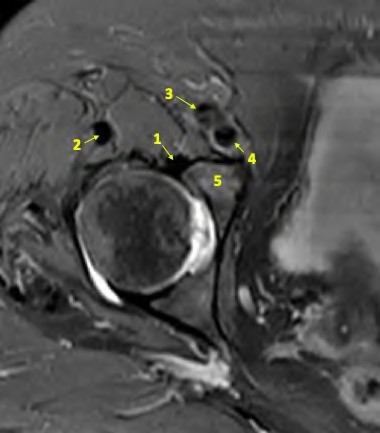

A 75-year-old man underwent total hip arthroplasty 10 years ago. He now reports mild groin pain which has been increasing lately. What is the most likely explanation for the finding in Figure A indicated with the arrows?

Osteolysis of the pelvis is a common complication associated with total hip arthroplasty. Osteolysis affects sockets with and without cement, and has been attributed to the biologic reaction to wear debris. With well-fixed cementless sockets, an expansile pattern of osteolysis is usually seen.

The radiographic appearance has a radiolucent area that starts at the implant-bone interface and expands into the cancellous bone away from the implant.

This pattern of osteolysis can be explained with the concept of effective joint space. This concept states that joint fluid and wear particles will flow according to pressure gradients and follow the path of least resistance.

The Level 5 review article by Chiang discusses osteolysis in further depth.